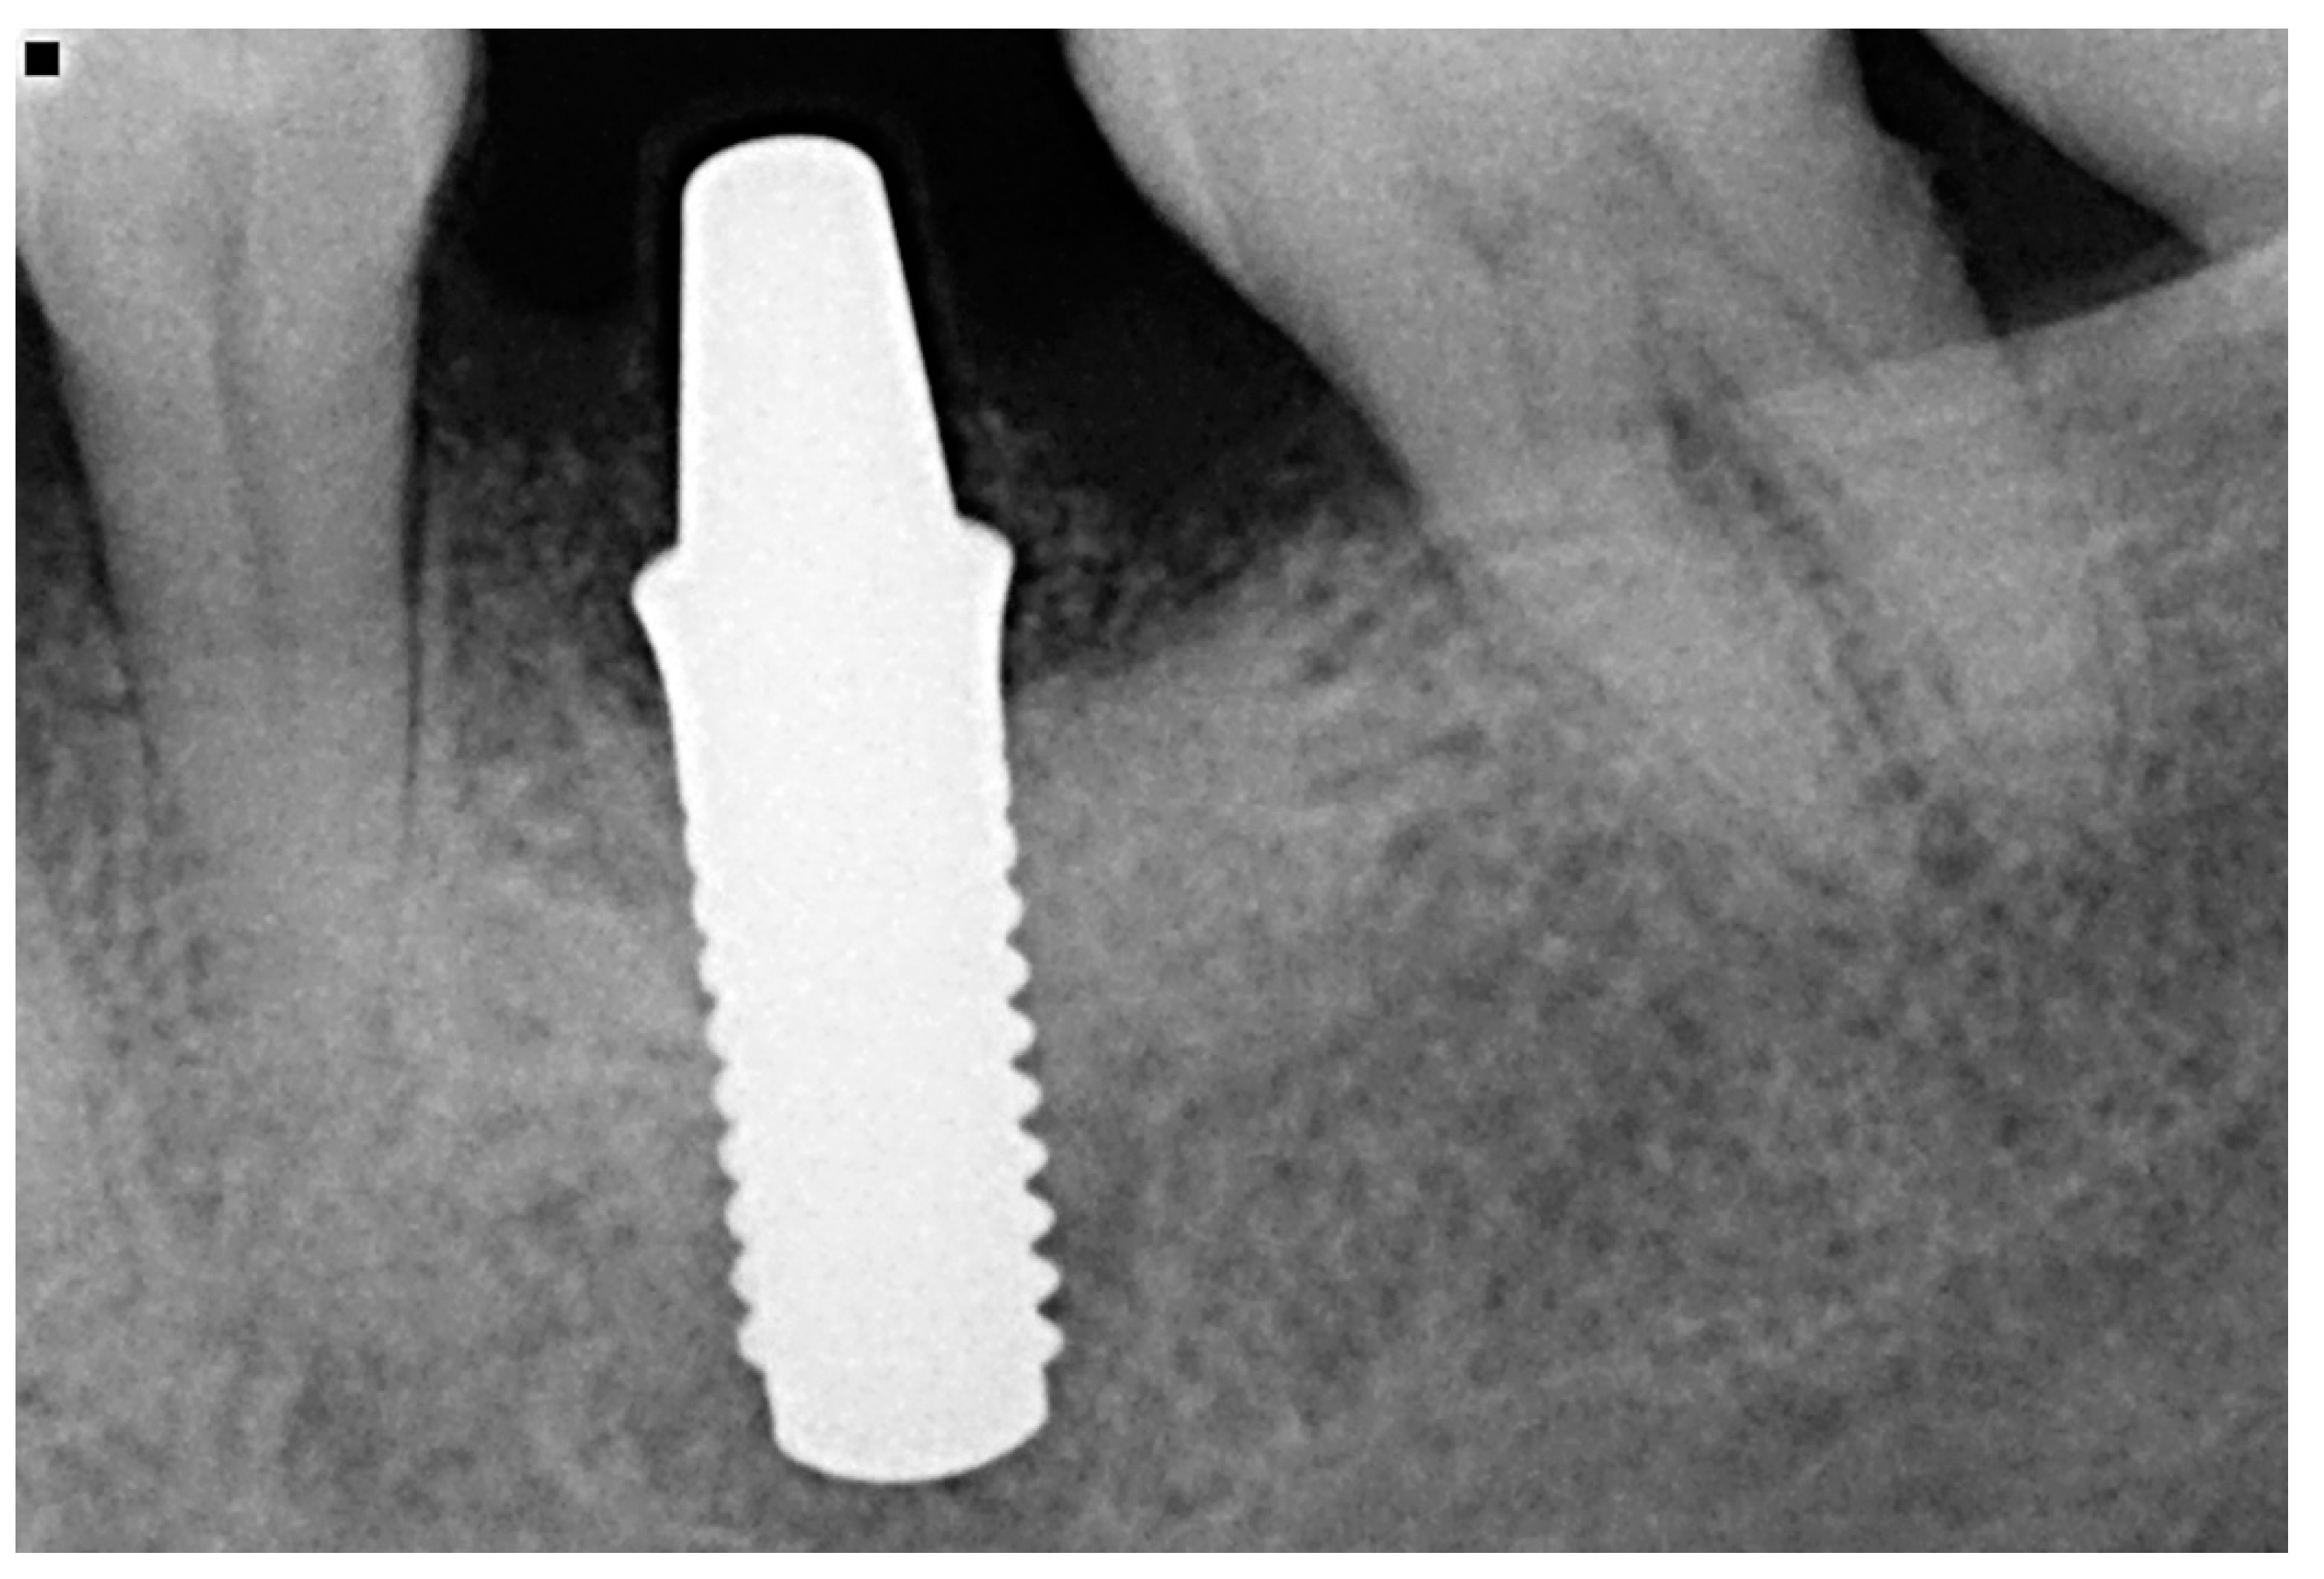

Lastly, Figure 7 and Figure 8 show a definitive ceramic restoration in another case located in the maxillary left first premolar space and its corresponding intraoral X-ray view, after three years of follow-up.

Figure 8. Intraoral X-ray view after three years of follow-up.